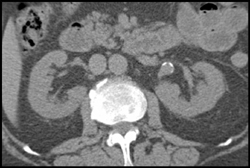

Left Renal Artery Aneurysm